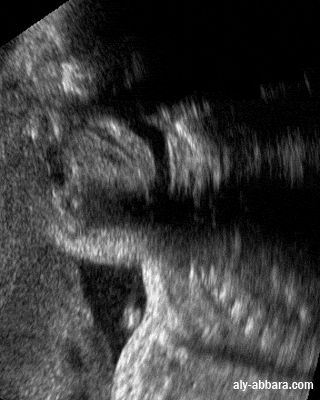

• Image échographique statique montrant une coupe sagittale passant par la cavité buccale et le pharynx, elle met en évidence la position anatomique et le rôle physiologique de la luette, un appendice charnu, mobile et contractile, prolongeant le bord postérieur du voile du palais et qui contribue à la fermeture du rhinopharynx pendant la déglutition.

• Fœtus de 32 semaines d'aménorrhée.